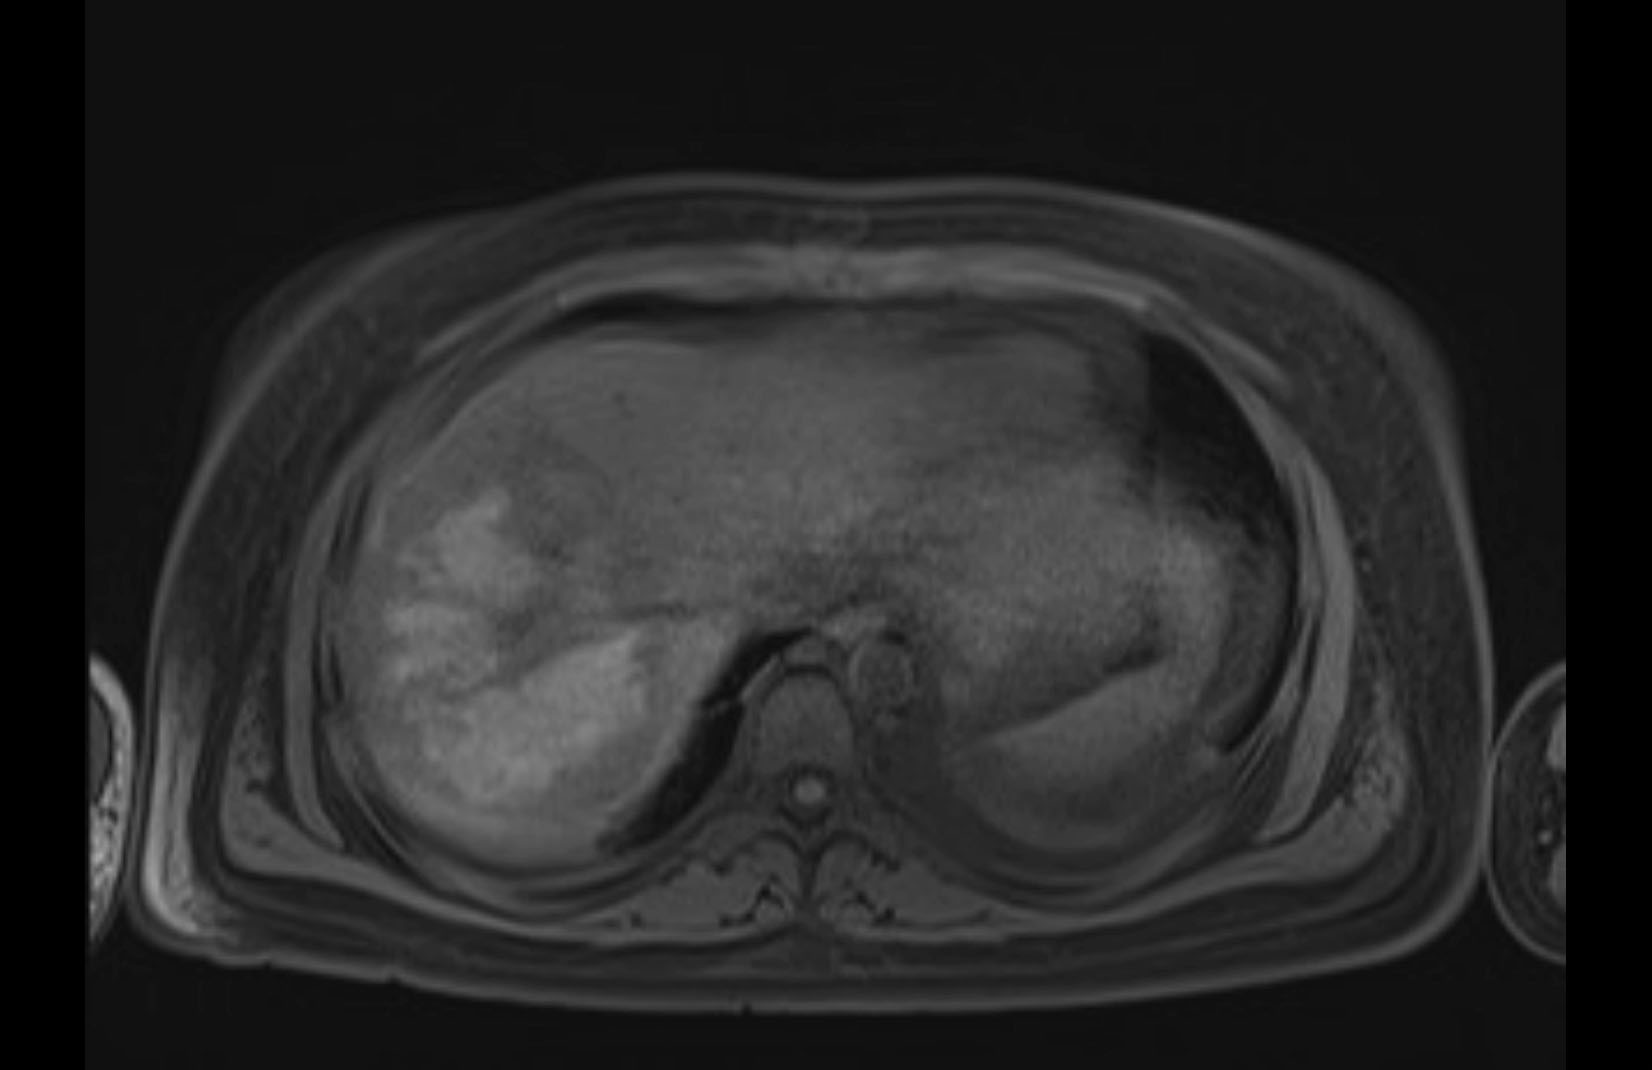

Imaging Analysis

Look through the patient's CT scan to identify any areas of concern for the necessary procedure.

MRI T1

MRI T2

Based on initial findings, which issue(s) would you be most concerned about?